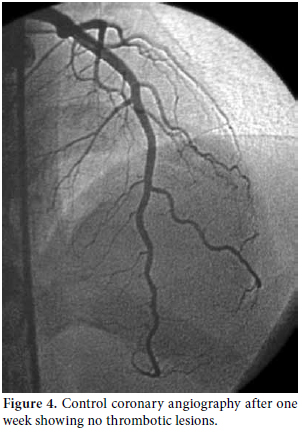

Consultations were then held with the pulmonary medicine and rheumatology departments regarding the eosinophilia identified in the CBC, pulmonary opacities revealed via chest X-ray, and the patient's past history of asthma (Figure 3). Furthermore, cranial computed tomography (CT) was performed on the day after the angiography which showed neurological involvement or paranasal sinus abnormality with a prediagnosis of CSS. The results of the cranial CT were also consistent with chronic sinusitis. The presence of asthma, hypereosinophilia of >10%, chronic sinusitis, and pulmonary opacities represent four of the six ACR criteria required for the diagnosis of CCS.[5] Our patient tested negative for anti-nuclear antibodies (ANAs), anti-double stranded DNA (antidsDNA), extractable nuclear antigens (ENAs) and anti-neutrophil cytoplasmic antibodies (ANCAs). The corticosteroid methylprednisolone at an initial dosage of 80 mg per day (1 mg/kg/d) was prescribed after the termination of the tirofiban infusion. Afterwards, the patient's eosinophil levels in the CBC decreased to normal ranges, and symptomatic relief was completely provided. Control coronary angiography was performed one week later, and the thrombotic lesions had disappeared (Figure 4). In addition, chest radiographs showed complete resolution of the opacities (Figure 5). After two more weeks, control echocardiography was performed revealing a normal morphology of the ventricles without any segmental wall motion abnormalities. Furthermore, the pericardial fluid had also disappeared.

Immunosuppressive treatment with corticosteroids can result in the improvement of impaired cardiac contractility and resolution of pericardial effusions, and this is exactly what happened with our patient after the control echocardiography revealed normal morphology of the ventricles without segmental wall motion abnormality along with no pericardial effusion.